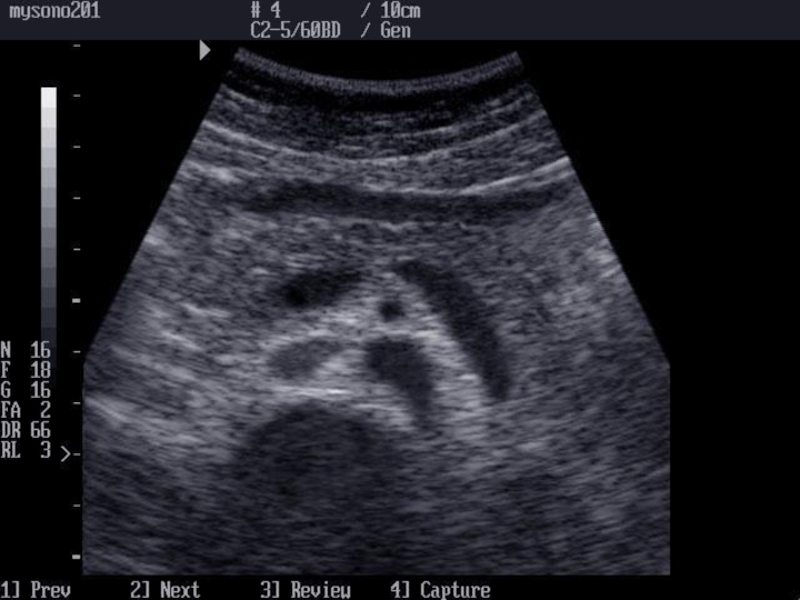

Слайд 8УЗИ поджелудочной железы

определяют воспалительные заболевания, аномалии развития, хронический и острый

панкреатит  и его осложнения, неопухолевые (кисты, жировая инфильтрация) и опухолевые

доброкачественные и злокачественные поражения.

УЗИ поджелудочной железы определяют воспалительные заболевания, аномалии развития, хронический и острый панкреатит  и его осложнения, неопухолевые (кисты, жировая